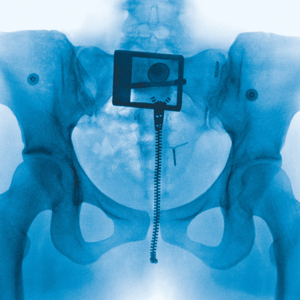

File: Lorde_-_Virgin.png (72 KB, 300x300)